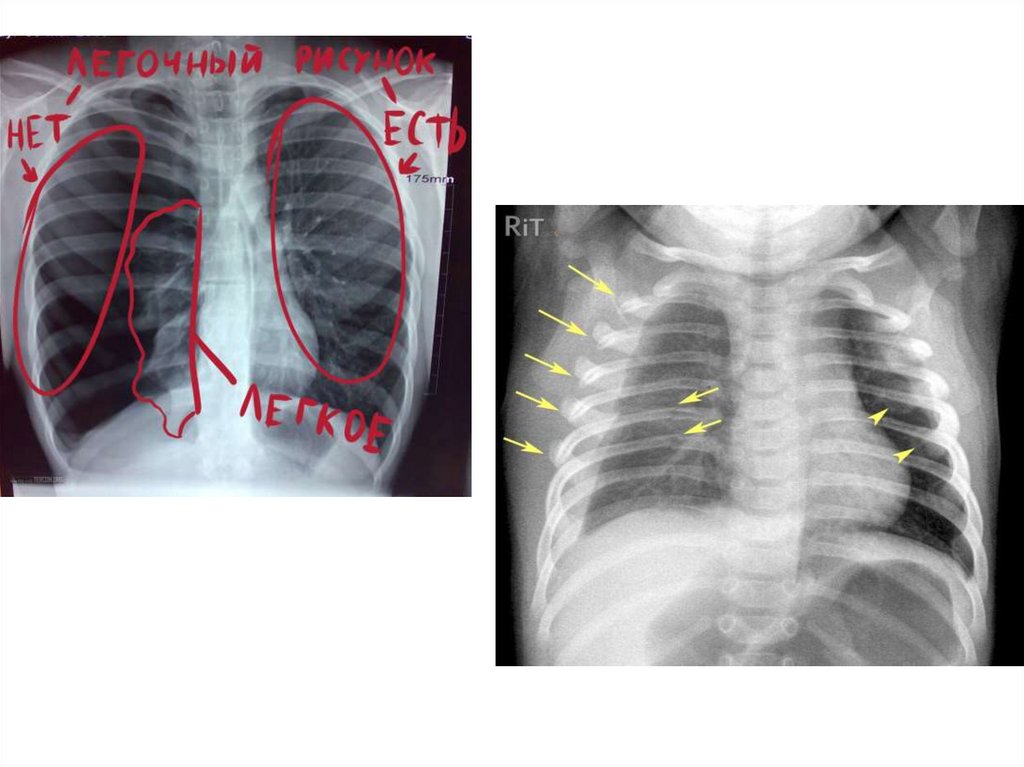

28. Современные инструментальные методы исследования: рентгенография грудной клетки. Особенности рентгеноанатомии грудной клетки.

Современные инструментальные методы исследования: рентгенография

грудной клетки. Особенности рентгеноанатомии грудной клетки.

Рентгенография - медицинское

неинвазивное исследование,

основанное на получении

суммационного проекционного

изображения анатомических структур

организма посредством прохождения

через них рентгеновских лучей и

регистрации степени ослабления

рентгеновского излучения на пленке

или бумаге.

Норма

Переломы ребер